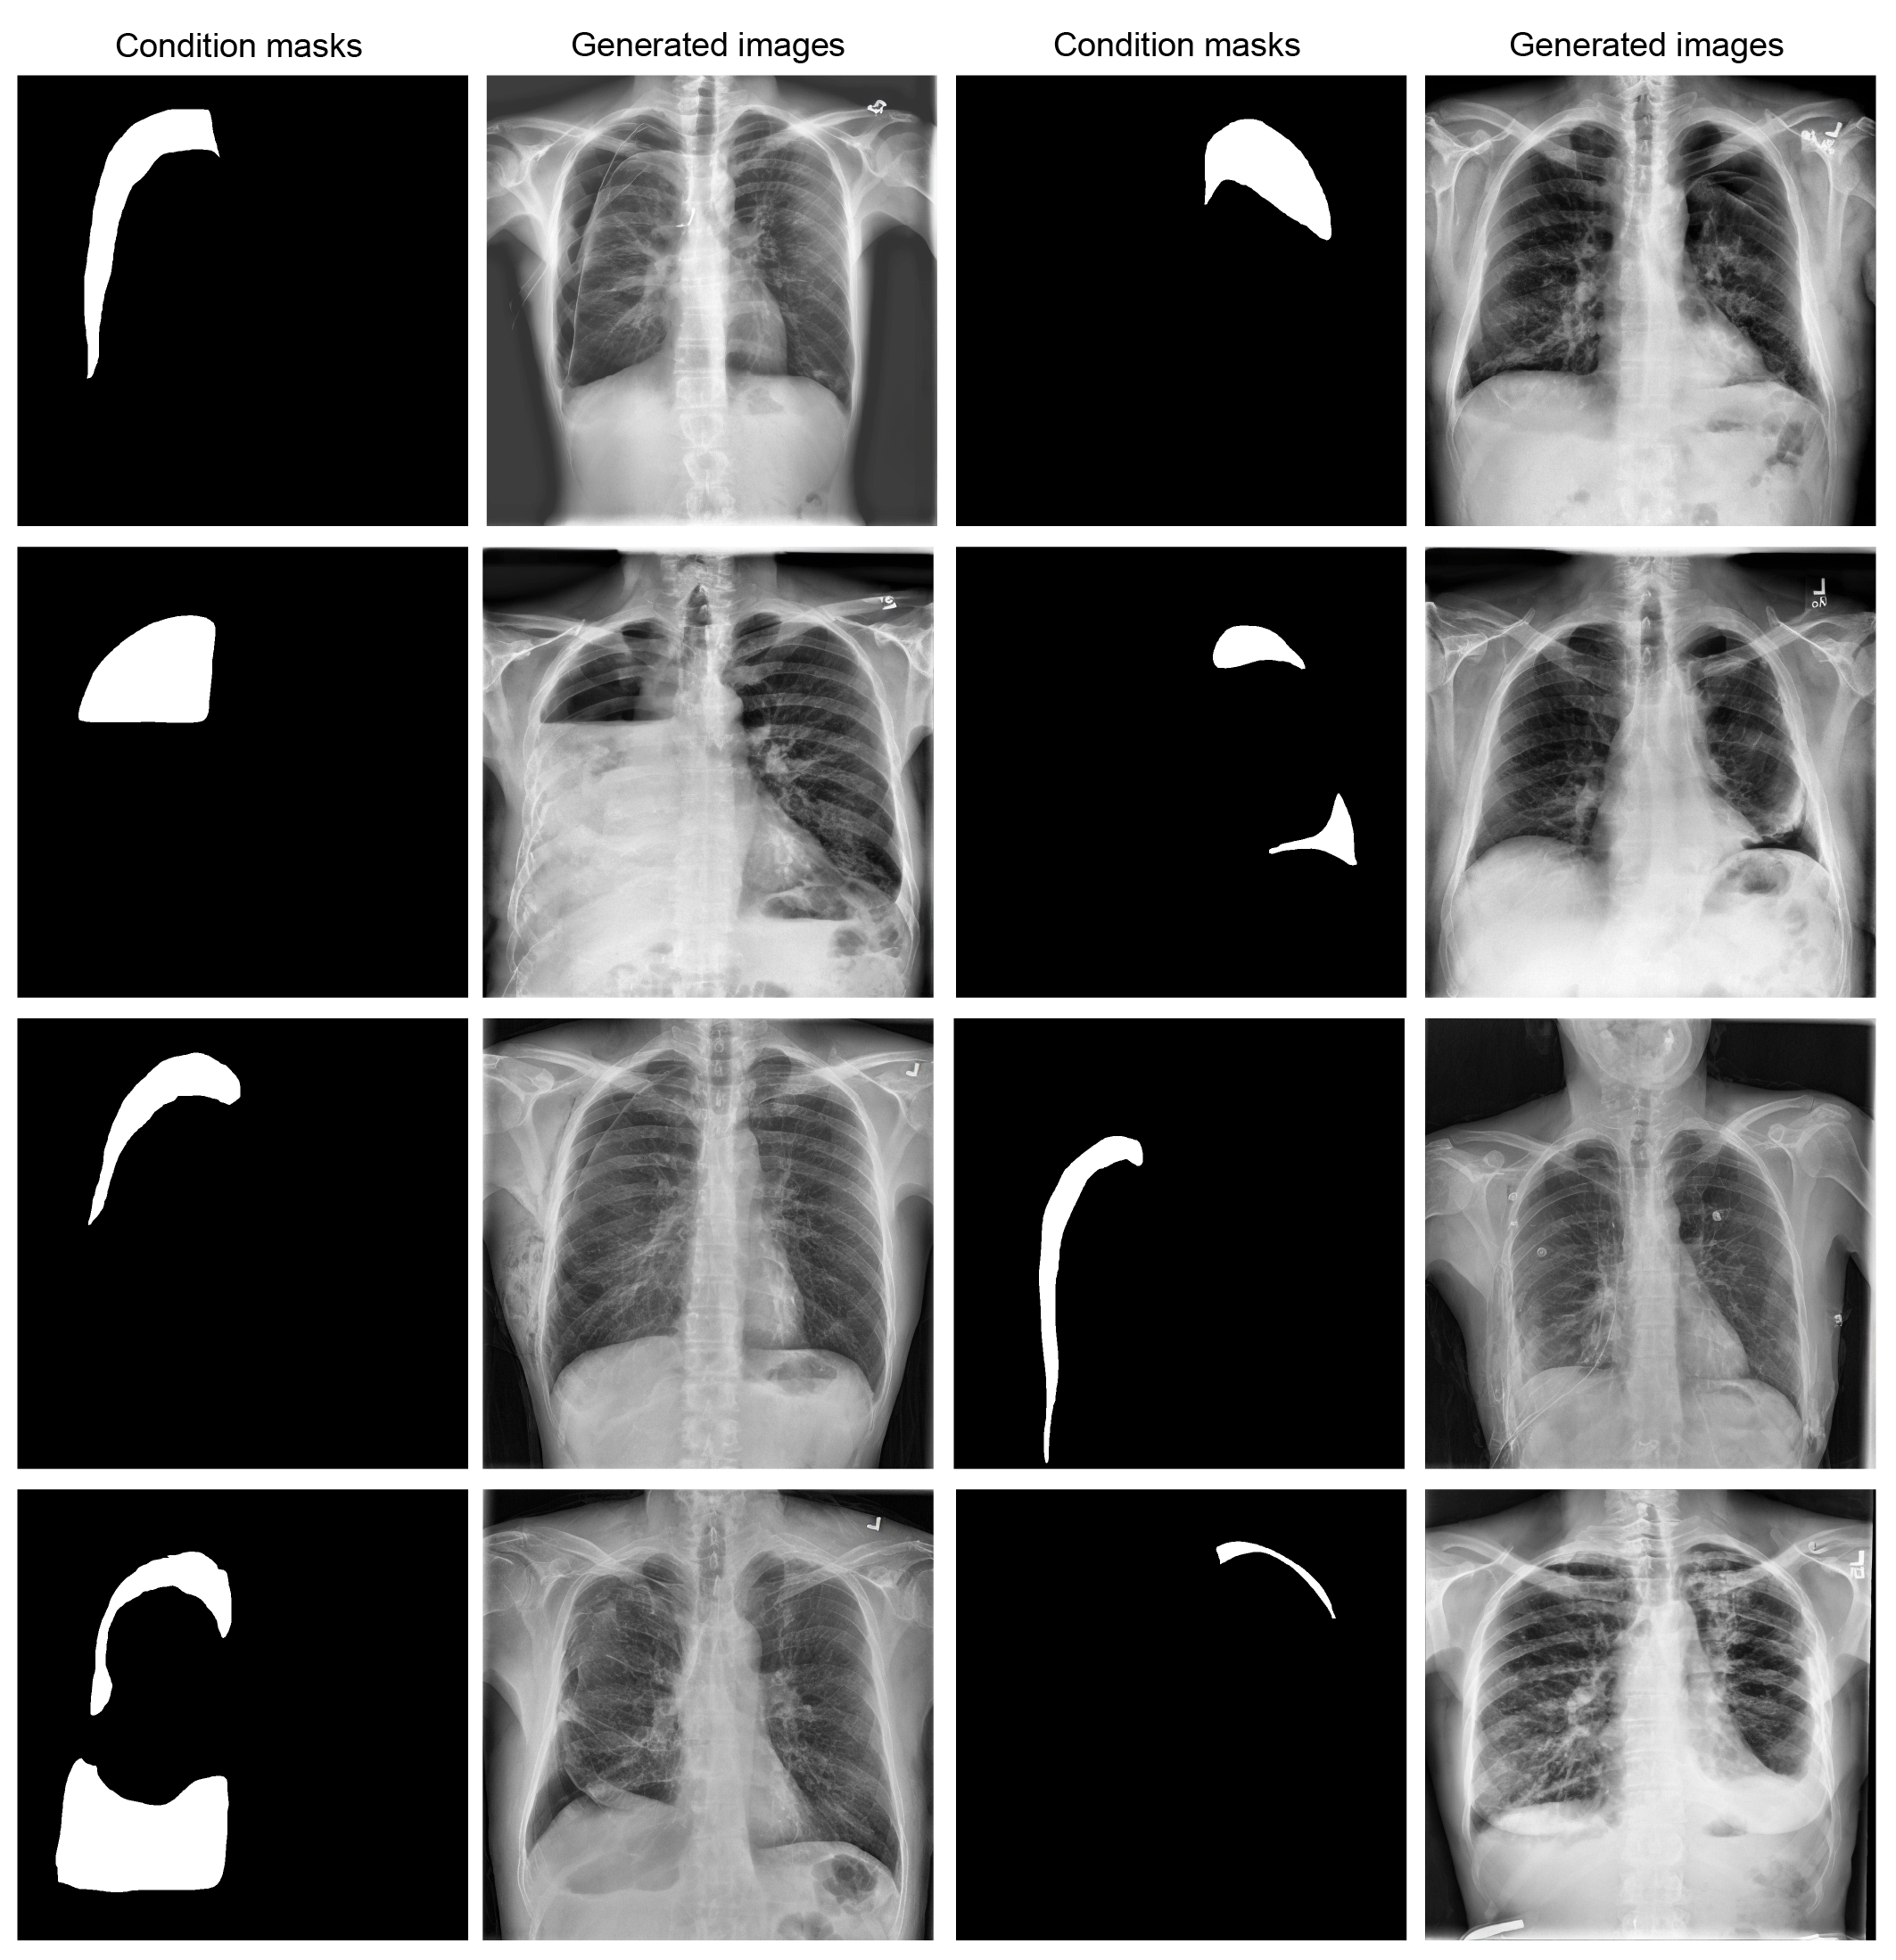

Building on a robust text-to-image foundation, we further enhanced ChexGen for annotation-to-image generation through the integration of ControlNet[10] and fine-tuning with fine-grained spatial annotations. This enhancement enables precise spatial control over pathology in relation to anatomical structures, allowing disease conditions to appear at any user-specified location in the generated image. This is a unique capability that existing generative models[13, 3] are unable to achieve, thereby broadening the scope of controllable medical image synthesis beyond text-only guidance (Methods).

For each task, we employed task-specific conditional inputs to generate synthetic images (Figure˜3b). For example, radiology report impressions served as prompts for classification tasks, while anatomical masks and bounding box annotations guided image generation for anatomical segmentation and disease detection tasks, respectively. Additional examples are shown in Extended Data Figures 78910. Each generated image was paired with its corresponding condition annotations, and the resulting synthetic dataset was combined with real data for training. Further details regarding the experimental design and dataset configurations are provided in Extended Data Table 3 and the Methods section.